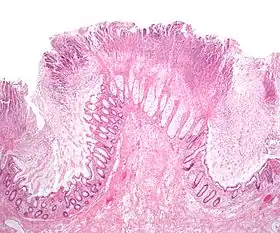

![]() صورة مجهرية لالتهاب القولون الغشائي الكاذب | |